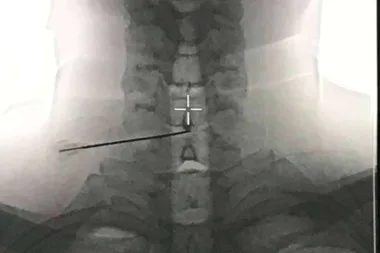

Ozonoterapia para hernia discal; el resultado se mantuvo 10 años después de la disolisis en el 88% de los casos